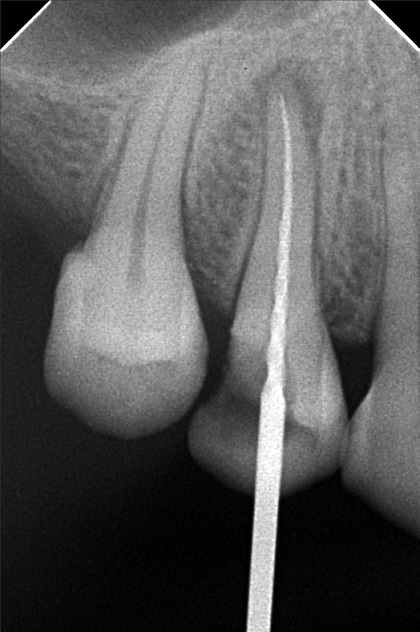

Edit Record Check our patient data records. Add patient information Patient Info Profile picture Last Name First Name Middle Name Birthdate Age Street Barangay City Country Zip Code Contact number Email Procedure 3/22/22- OP Lc 13 m/ 21 d/ 22 m/ 47 o/ b/ cervical xray 14 for rct 10/11/22 - OP (L); ACCESS #14, SCOUT #10 BL 18mm, EUGENOL. 10/14/22- 12/11/21/22- TF emax veneers 10/19/22 - 19mm, close w/ pulp devitalizer 09/02/23- op ** For change of crowns posterior Lower for Crown #15 08/13/24 OP 01/23/26 Alumina crwon #14 temporary crown OP Scanning File bangaros.jpg File 2 bongaros.jpg File 3 bongaros_02.jpg File 4 bongaros_03.jpg File 5 bongaros_04.jpg File 6 309497615_1081002115924778_349479569281481267_n.jpg File 7 bongaros_1.jpg File 8 bongaros_02_1.jpg File 9 File 10 File 11 File 12 File 13 File 14 File 15 File 16 File 17 File 18 File 19 File 20 Retain Record Retain Record Yes No Save Your Changes